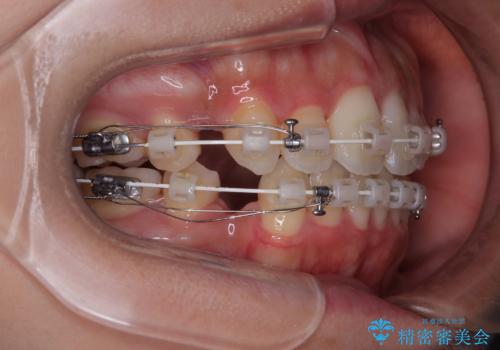

- 審美装置

- 1年10ヶ月

- 口元の突出感と口の閉じにくさを気にして来院された患者様です。

上下左右第一小臼歯4本を抜歯し、ワイヤー装置にて口元を引っ込めるよう矯正治療を行うこととしました。

口元の突出感が改善されてことで、下唇に引っかかっていた上顎前歯も気にならなくなりました。